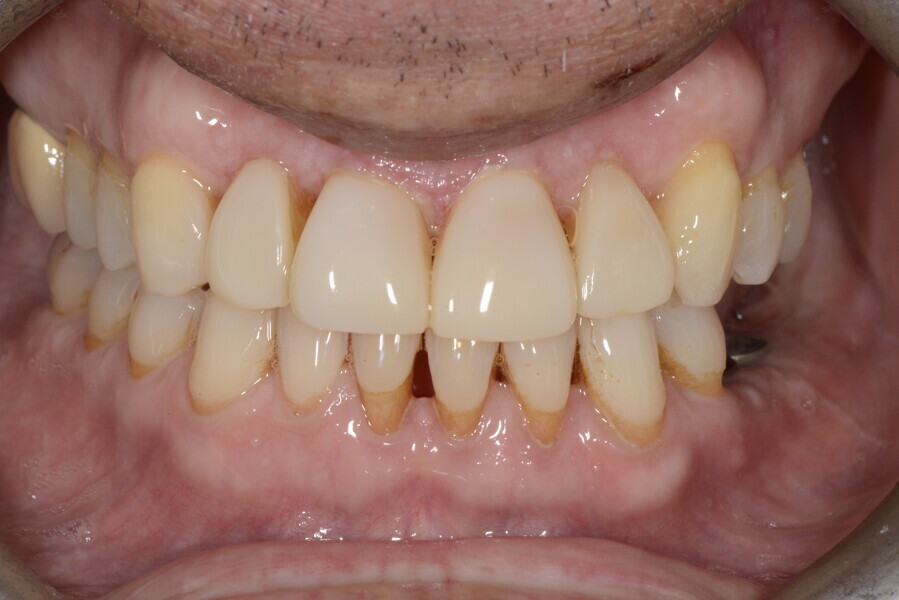

After the first phase of aligner treatment, we had achieved better inter-arch coherence, better maxillary arch expansion, and some space for improving the anterior tooth proportions restoratively (Fig. 19). We then temporarily restored the anterior teeth directly with composite, closing the spaces, improving the tooth proportions and further increasing the maxillary arch expansion (Fig. 20). We used restorative arch expansion to reduce the orthodontic destabilisation of the teeth to achieve the correct inter-arch coherence and retain the teeth in the cortical bone.38 A refinement aligner phase was undertaken to improve the final alignment of the gingival zenith and to improve the inter-arch coherence (Fig. 21). The periods of the first orthodontic phase and of the refinement were used to augment the mandibular and maxillary bone and to place the implants (Fig. 22). At the end of the orthodontic treatment, the case was finalised with ceramic veneers in the anterior area and temporary restorations on the implants in the posterior area (Figs. 23–26).

The provisional phase of about four months was important to allow the peri-implant tissue to mature and to teach the patient to chew correctly with chewing gum, cotton rolls and silicone masticatory sticks. This is fundamental training for the patient to achieve the correct alternating unilateral masticatory cycle needed to obtain the ideal rehabilitation of the masticatory system. We wanted the patient to achieve ideal masticatory and swallowing function. After sufficient rehabilitation time, we finalised the case with posterior zirconia crowns screwed on to the implants (Fig. 27).26

Our ideal final rehabilitation goals were:

• posterior stability;

• inter-arch coherence and U-shaped arches;

• anterior freedom during mastication;

• minimum disclusion vertical dimension;

• alternating unilateral masticatory cycle;

• physiological swallowing and high tongue posture against the palate; and

• mandibular disclusion advancing the mandible freely.

For maintenance purposes, after prosthetic finalisation, the patient was to carry on with the Froggymouth therapy and to use the Ri.P.A.Ra. for physiotherapeutic exercises and mastication training (Fig. 28). It was strongly recommended that the patient wear a mandibular occlusal splint during sleep. This occlusal splint was designed with disclusion guides to advance the mandible and ensure balanced contralateral support (Fig. 29).11, 39 We achieved an aesthetic appearance with adequate inter-arch coherence and a better cephalometric result (Figs. 30 & 31).